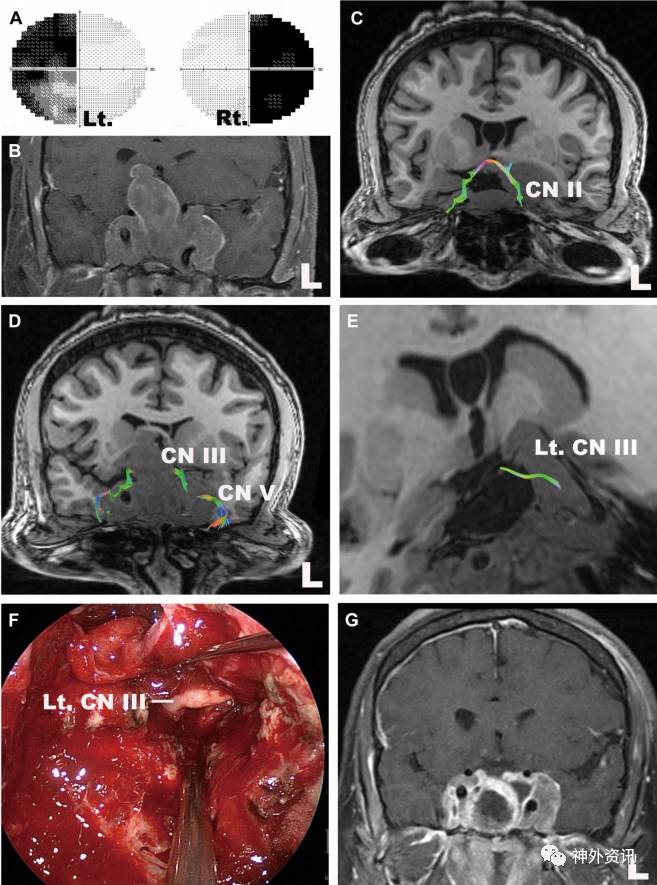

图12. 巨大垂体腺瘤。A.视力检查显示,完全性双颞侧偏盲;B.术前MRI(冠状位);C.视神经和视交叉(冠状位);D.动眼神经和三叉神经(冠状位);E.左侧动眼神经(斜位);F.术中图像显示,动眼神经完全被海绵窦近侧肿瘤包裹;G.术后MRI(冠状位)。